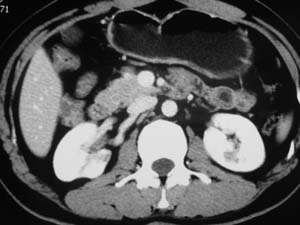

以下是引用子期在2010-3-19 20:47:00的发言:[br]血管畸形的ct增强应该有明显强化,本例并不相符合。本例双肾局部的略低密度影,累及肾盂,局部皮质明显变薄、内陷,增强扫描有轻度的强化,应考虑为炎性病变,患者为年轻男性,累及双肾的感染以结核较常见,可以没有明显的临床症状,尿中有时候也并不能查出什么;肾脓肿常有明显感染中毒症状,本例不符,另外一般的肾盂肾炎或肾小球肾炎通过小便就可确诊,其它还不能排除的是黄色肉芽肿性肾盂肾炎,然而单凭ct一般也很难鉴别。